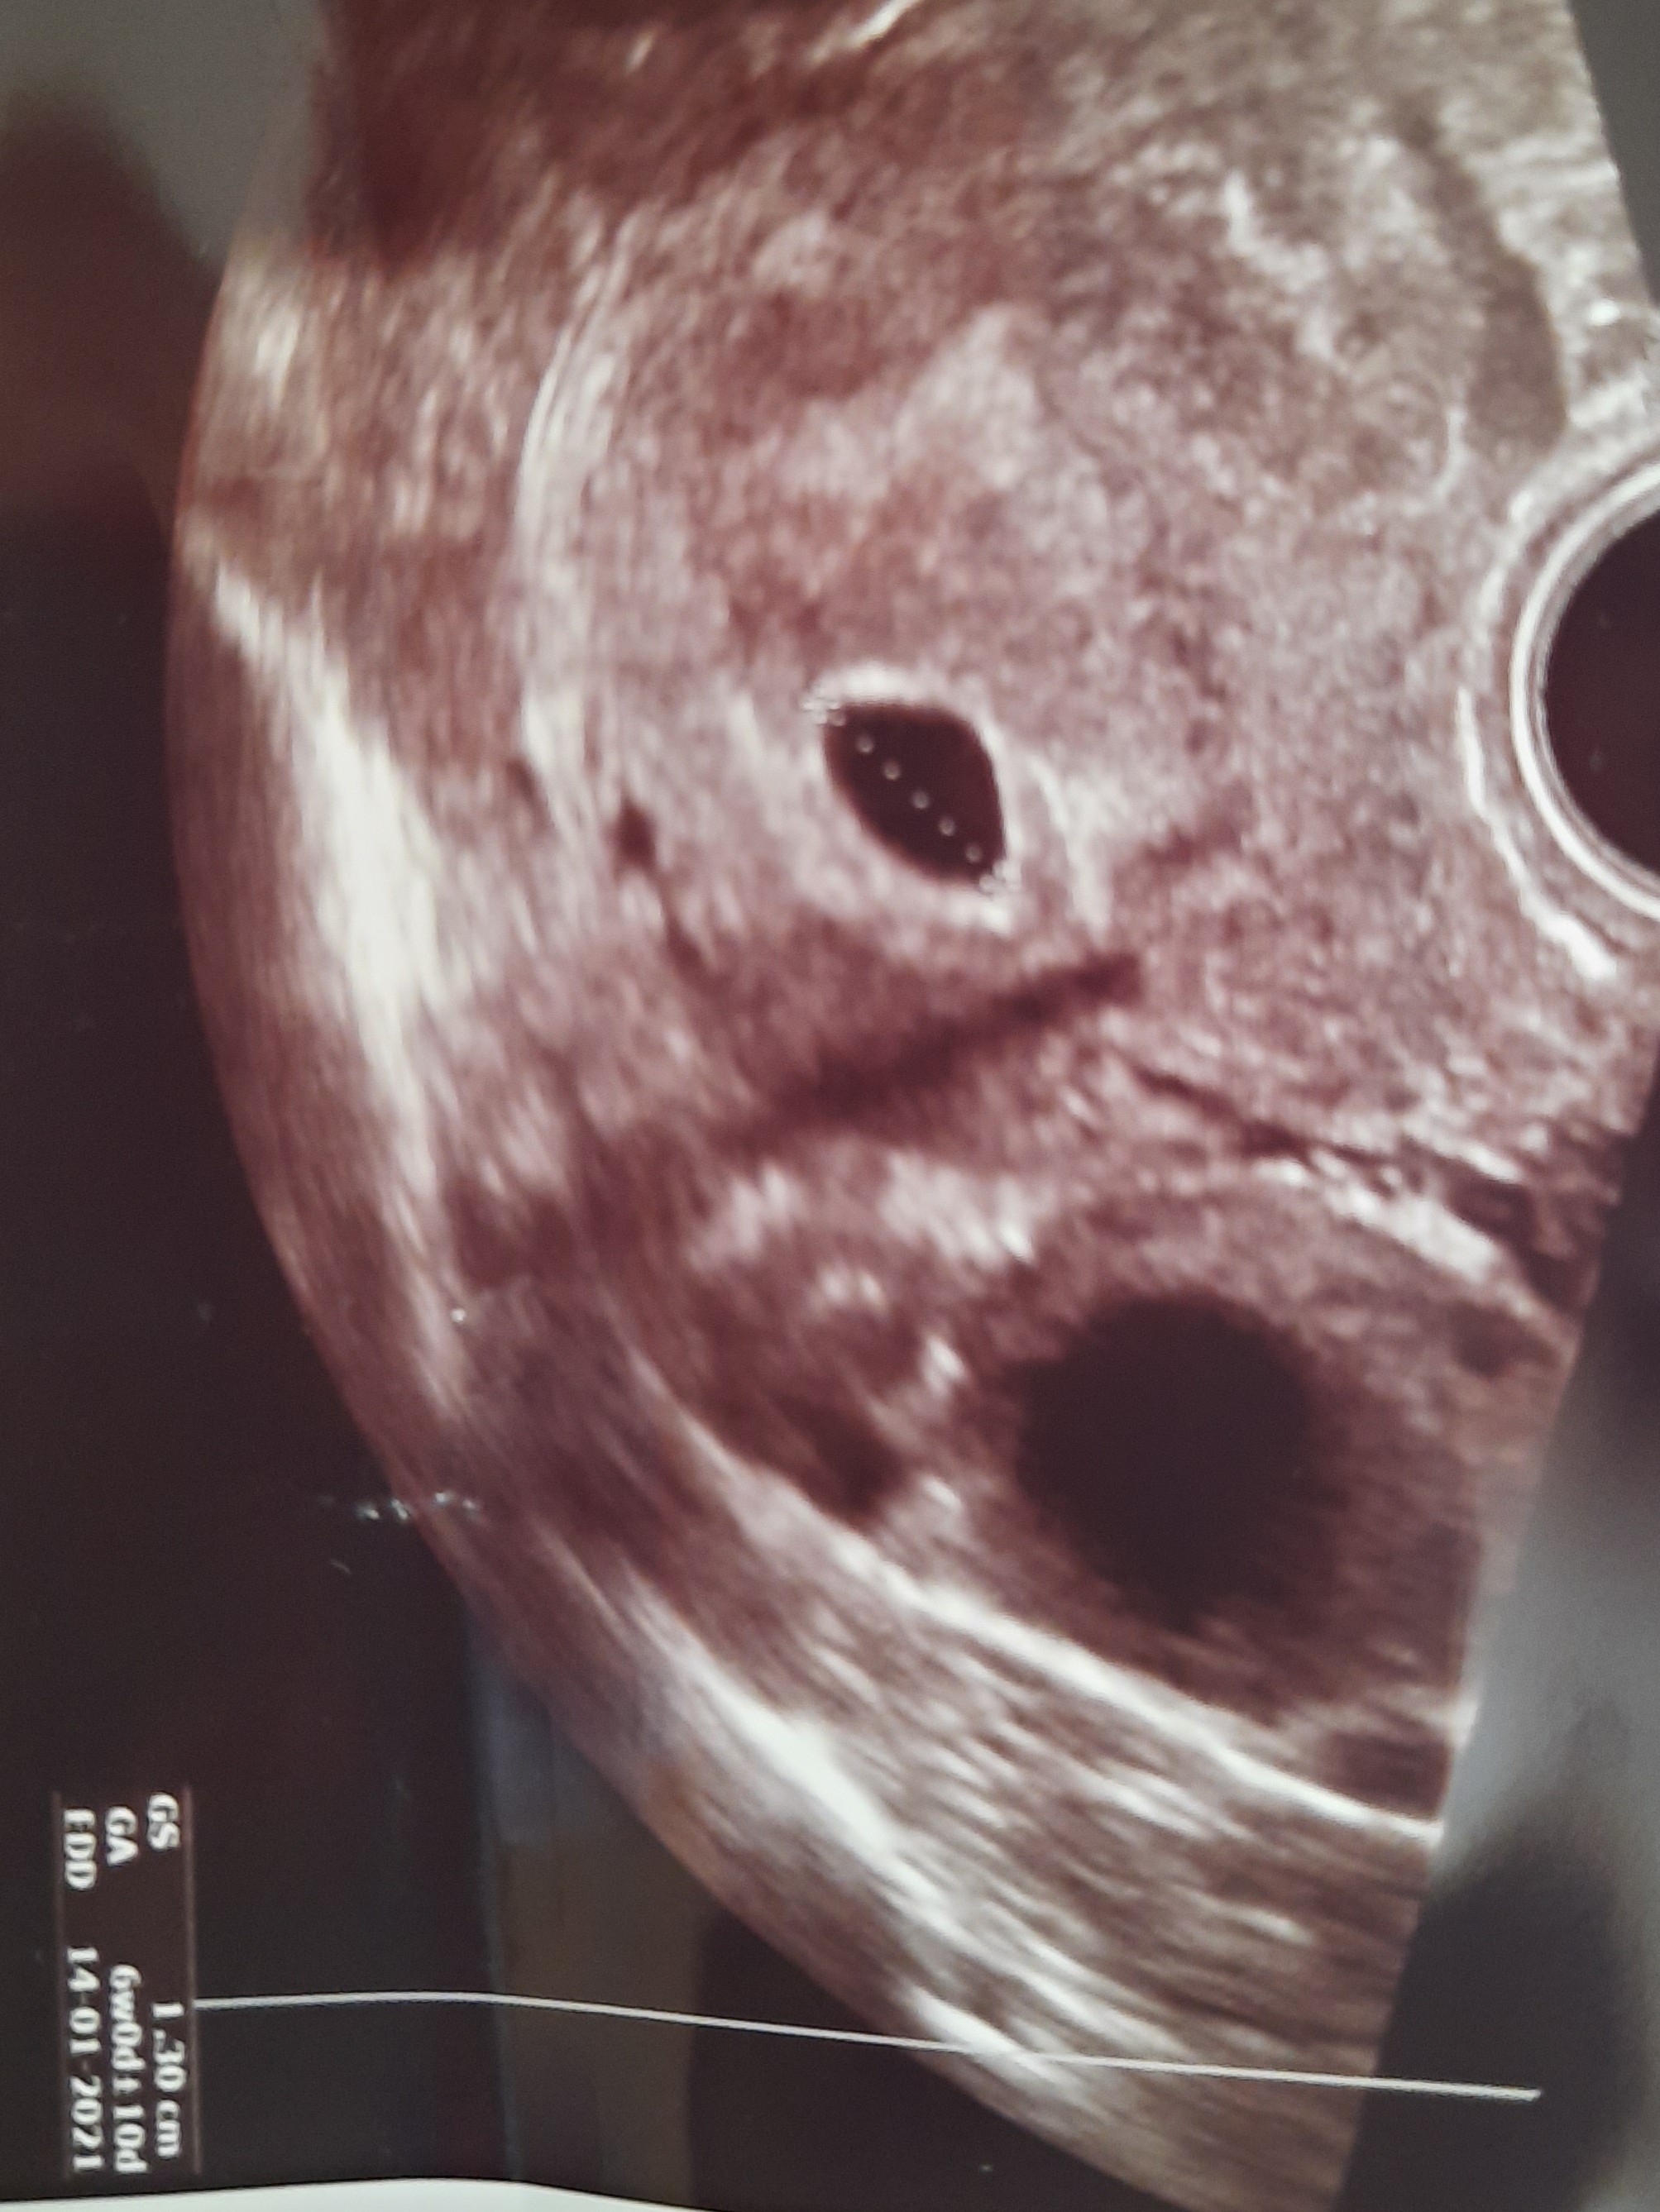

Ot już cyknęłam na telefonie to proszę. Pęcherzyk miał 13mm.Ok. Dziękuję![]()

Edit: Duża czarna plama to torbiel i mi też w związku z tym zalecono leżeć i łykać duphaston.

Bidulko, jeszcze torbielOt już cyknęłam na telefonie to proszę. Pęcherzyk miał 13mm.